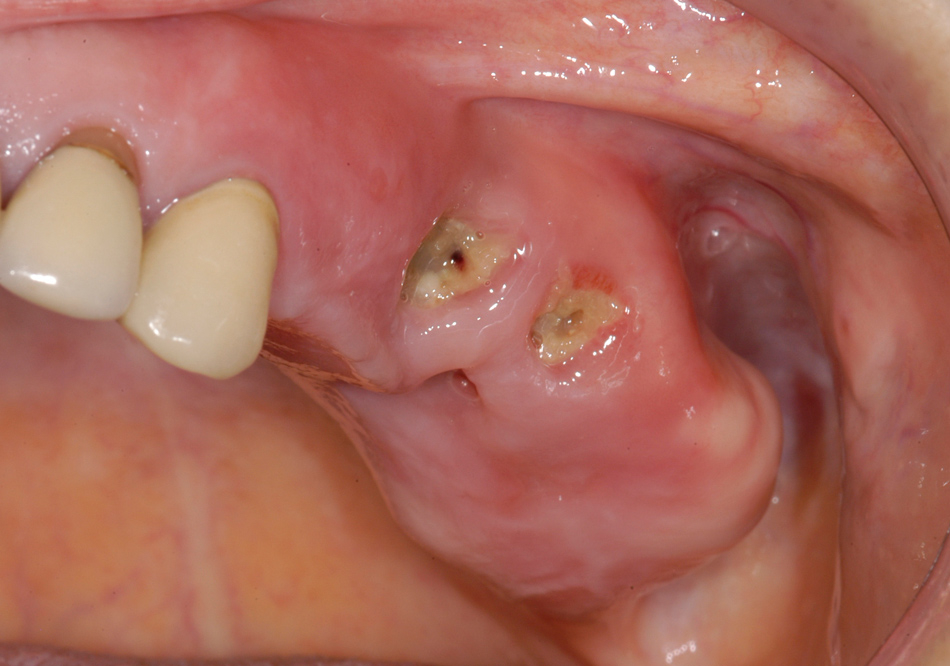

Figure 2

Female patient with osteoporosis and BRONJ of the left posterior maxilla including the maxillary sinus. The clinical picture shows exposed bone with signs of infection of the surrounding and pus discharge.

The majority (75%) of patients presented with pain as their major concern. All patients showed signs of infection in the area of the affected jaw, which involved pus discharge, abscess formation, or inflamed surrounding soft tissue (fig. 2).

Exposed bone was observed in only 74% of patients; 23% of patients presented with a fistula, but without clinically evident exposed bone (only radiologically evident affected bone) (fig. 3a and b). All of those patients except one were treated surgically; therefore, the diagnosis of osteopathology of the jaw was also affirmed clinically.